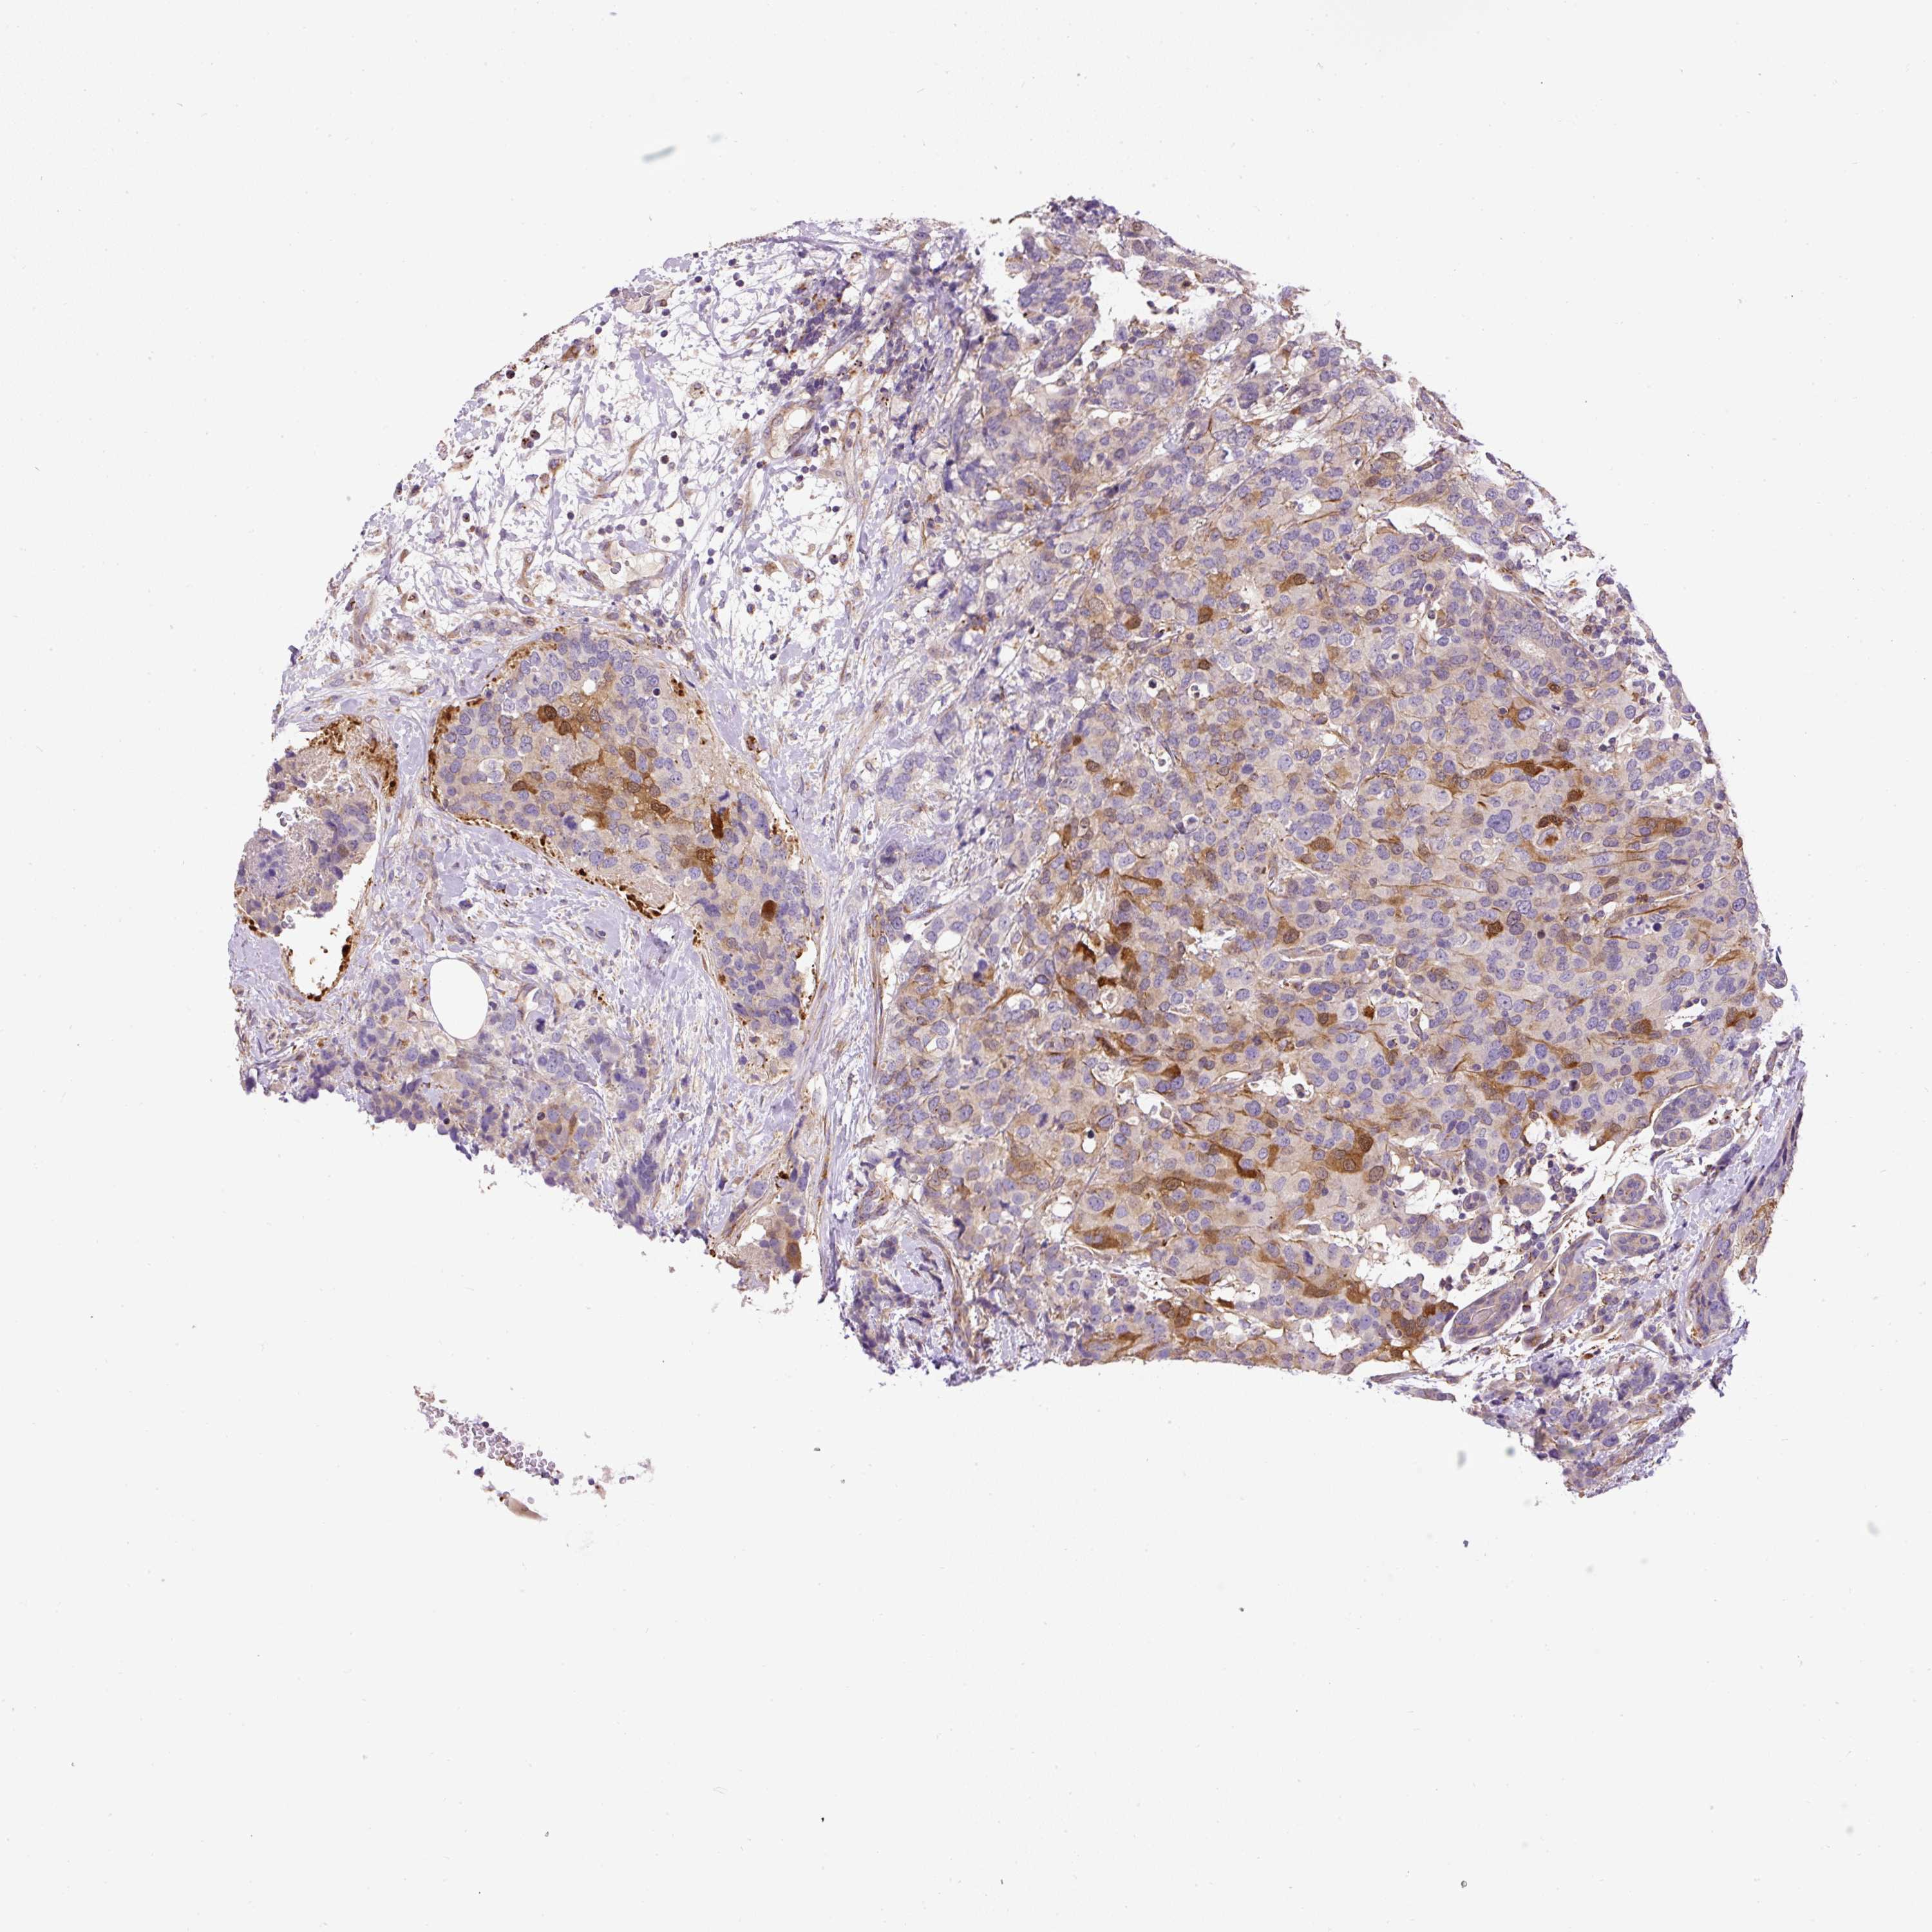

CANCER BREAST CANCER Show tissue menu

BRCA TCGA BRCA VALIDATION PROTEIN EXPRESSION